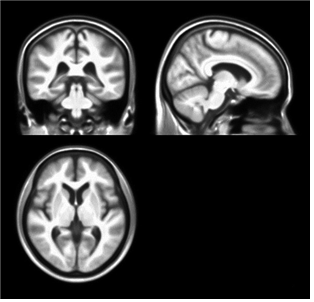

서울의대 김기웅 교수(분당서울대병원 정신건강의학과)가 뇌질환이 없는 60세 이상 정상 노인 96명의 MRI를 분석해 '한국 노인의 표준 뇌'를 개발했다고 21일 발표했다.

이러한 문제를 해결하려고 김 교수는 60세 이상의 우리나라 노인 96명의 MRI 영상으로 '한국 노인'의 표준뇌를 개발하게 된 것이다. 한국노인의 뇌 모양을 대표하는 표준뇌인 만큼, 뇌의 형태에 영향을 줄 수 있는 다양한 질환들을 포괄적이고 정밀한 임상 검사를 통해 철저히 배제하는 등 엄격한 대상 선정 과정을 거쳤다.

분석 결과 예상대로 서양인의 표준 뇌와 한국 노인의 표준 뇌는 크게 달랐다. 좌우 폭의 경우 한국 노인이 약간 넓고 앞뒤 길이와 상하 높이는 서양인이 큰 차이로 길거나 높았다.